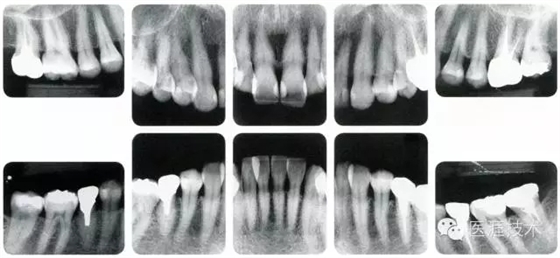

健康且正常的牙周組織臨床圖像

50歲女性的健康口腔內(nèi)部

圖為50歲女性,無特殊全身疾病,不抽煙。持續(xù)保養(yǎng)6年。無填充物等問題,依照患者本人要求持續(xù)觀察。牙周組織臉頰側(cè)雖見部分萎縮,但X線牙片顯示牙間無骨吸收現(xiàn)象,保持著比較健康的狀態(tài)。